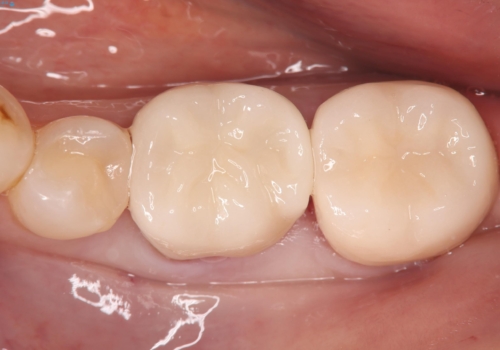

- ご友人との会話中などに、下の歯に入れてあるメタルインレーが見えてしまうのが気になり、やり変えを希望された患者様です。審美性、清掃性に優れたセラミックでの治療を希望されたため、セラミックインレー、クラウンで治療いたしました。

口を開けた際の見た目が向上し、非常に満足いただけました